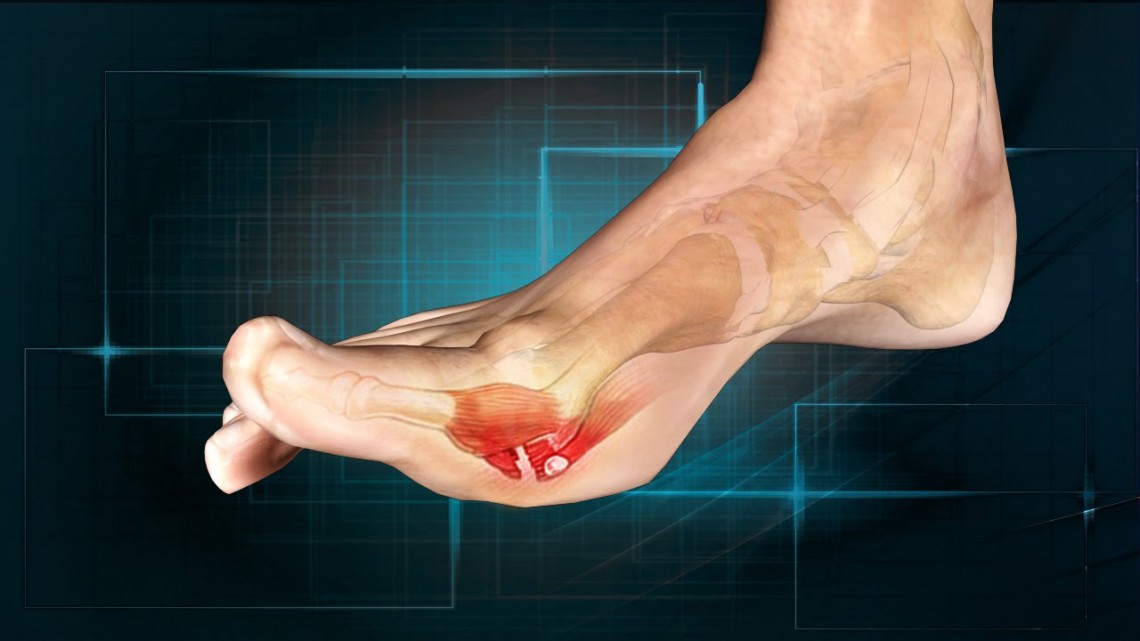

Does Turf Toe Go Away . Turf toe is a sprain of the big. Your recovery timeline and return to activity depend on the severity of your injury. The more severe the injury, the longer the recovery time will be. Grades 2 and 3 injuries take longer to heal. With severe injuries, surgery may be required. While it may sound minor, turf toe can have a significant impact on an individual’s. Sometimes complete recovery may not occur, leaving the patient with a stiff or arthritic toe. Varies depending on your pain tolerance. The recovery time for turf toe is dependent on the severity of the injury. Turf toe almost always goes away with proper treatment, such as rest and ice. Turf toe is a medical condition involving a sprain to the metatarsophalangeal (mtp) joint in your big toe. After a grade 1 turf toe injury, you can return to normal activities once your pain is under control. Turf toe happens when you bend your big toe up toward the top of your foot too far. Doctors grade turf toe injuries from 1 to 3 according to the extent of the damage to the. Treatment of turf toe will depend on how severe the injury is.

With severe injuries, surgery may be required. Your recovery timeline and return to activity depend on the severity of your injury. The recovery time for turf toe is dependent on the severity of the injury. After a grade 1 turf toe injury, you can return to normal activities once your pain is under control. Turf toe happens when you bend your big toe up toward the top of your foot too far. Sometimes complete recovery may not occur, leaving the patient with a stiff or arthritic toe. Doctors grade turf toe injuries from 1 to 3 according to the extent of the damage to the. While it may sound minor, turf toe can have a significant impact on an individual’s. Varies depending on your pain tolerance. This can cause you to sprain or injure your toe and the ligaments surrounding it.

Does Turf Toe Go Away Your recovery timeline and return to activity depend on the severity of your injury. The more severe the injury, the longer the recovery time will be. Turf toe happens when you bend your big toe up toward the top of your foot too far. Turf toe is a medical condition involving a sprain to the metatarsophalangeal (mtp) joint in your big toe. Turf toe is a sprain of the big. Varies depending on your pain tolerance. This can cause you to sprain or injure your toe and the ligaments surrounding it. While it may sound minor, turf toe can have a significant impact on an individual’s. Your recovery timeline and return to activity depend on the severity of your injury. Turf toe almost always goes away with proper treatment, such as rest and ice. With severe injuries, surgery may be required. Treatment of turf toe will depend on how severe the injury is. Sometimes complete recovery may not occur, leaving the patient with a stiff or arthritic toe. The recovery time for turf toe is dependent on the severity of the injury. Doctors grade turf toe injuries from 1 to 3 according to the extent of the damage to the. Grades 2 and 3 injuries take longer to heal.